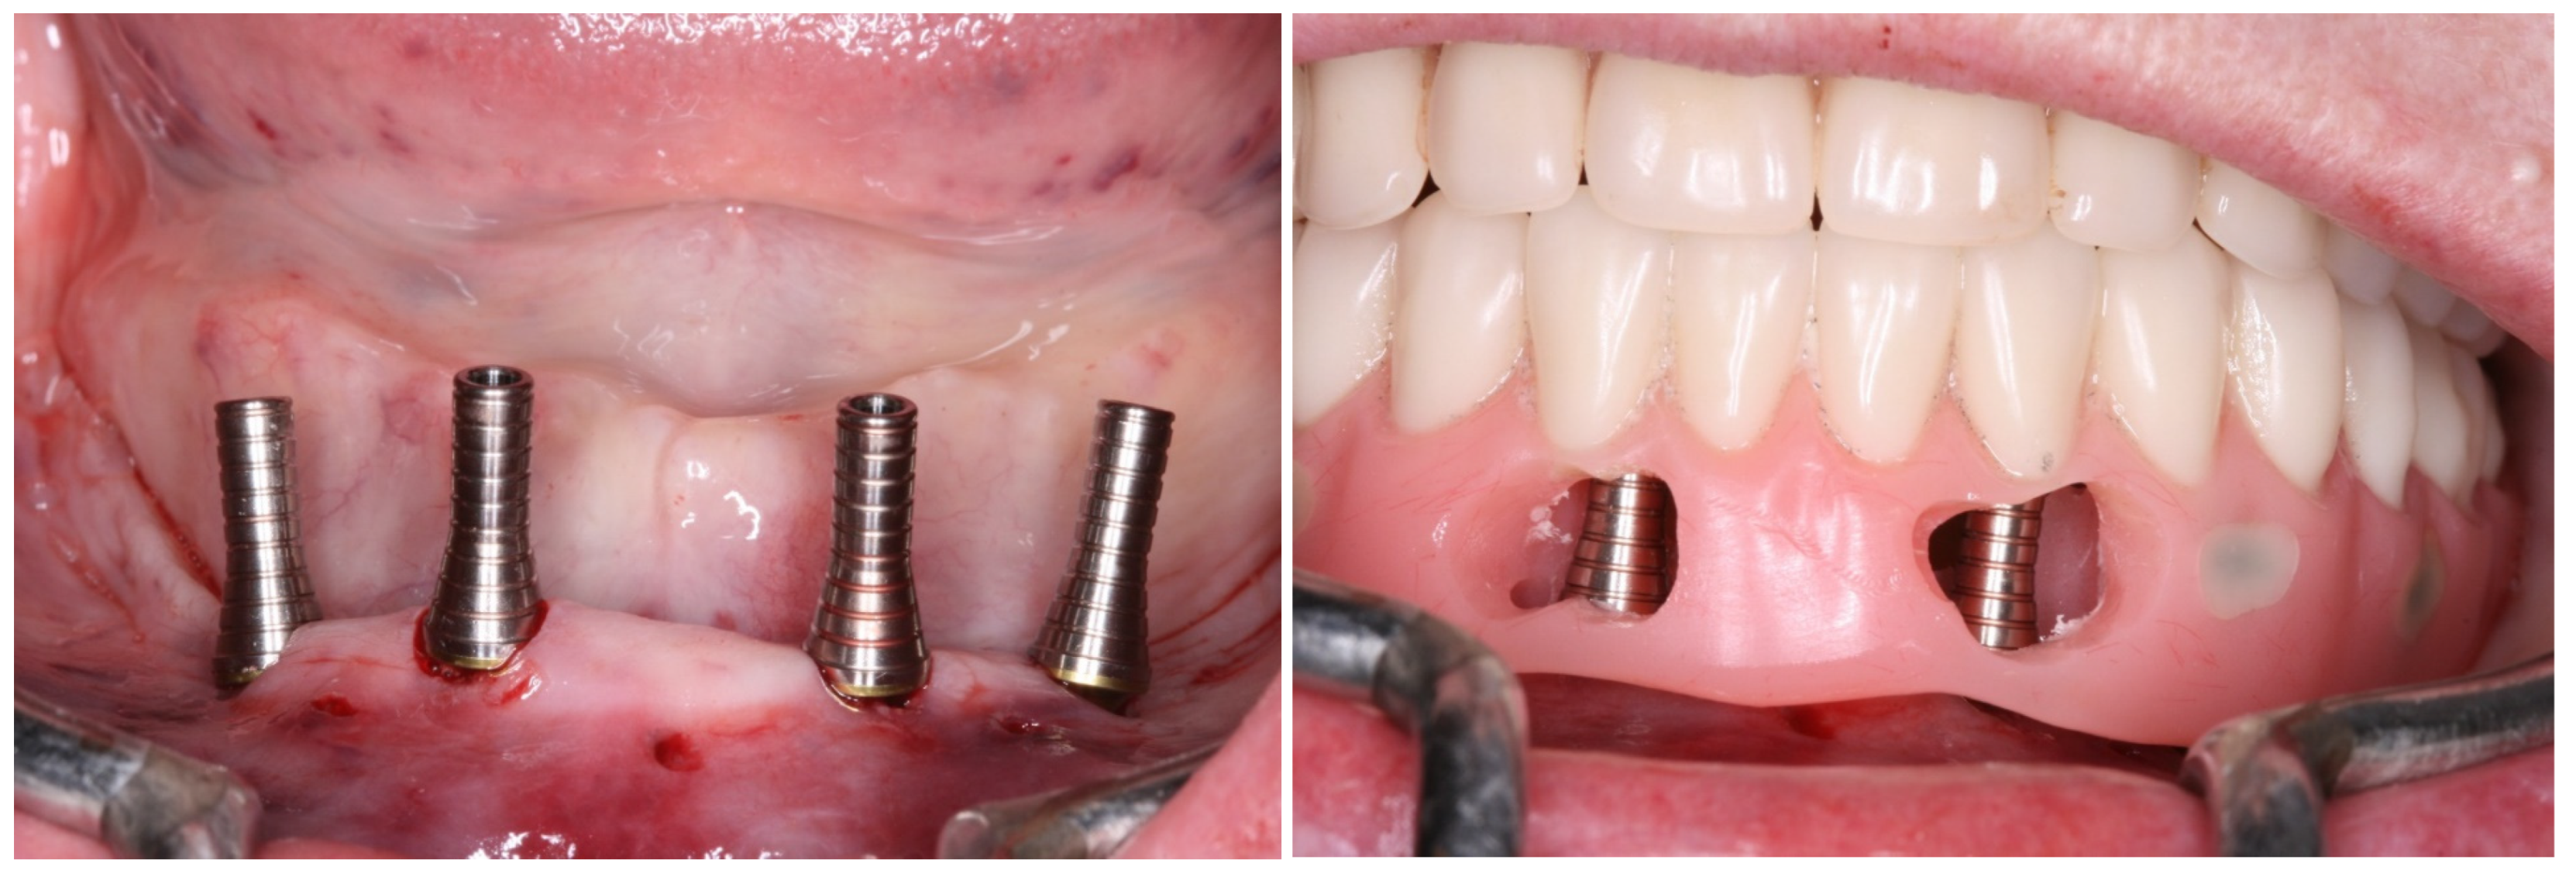

2. Case Report